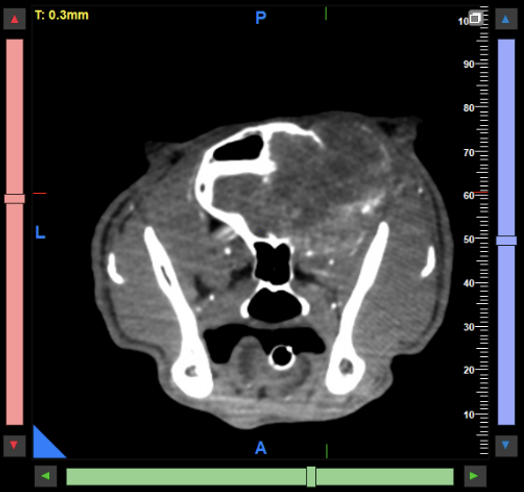

Abdomen: Ein wesentlicher Schwerpunkt unserer klinischen Arbeit liegt im Abdomen. Neben der Darstellung abdominaler Tumoren und struktureller Organveränderungen konnten auch Gefäßanomalien wie portosystemische Shunts erfolgreich dargestellt werden. Für viele klar definierte Fragestellungen stellt das CBCT eine praktikable und diagnostisch wertvolle Alternative zum MSCT dar (Abb. 5 & 6).